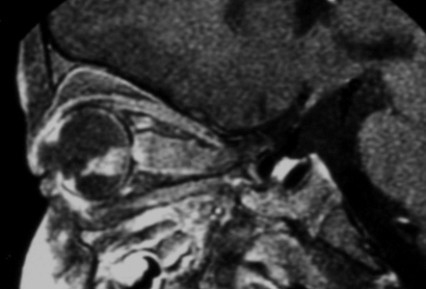

MRI pattern of retinoblastoma with optic nerve involvement (sagittal enhanced T1-weighted sequence)

Aerts I, et al. Orphanet J Rare Dis 2006 Aug 25; 1: 31; licensed under CC BY 2.0